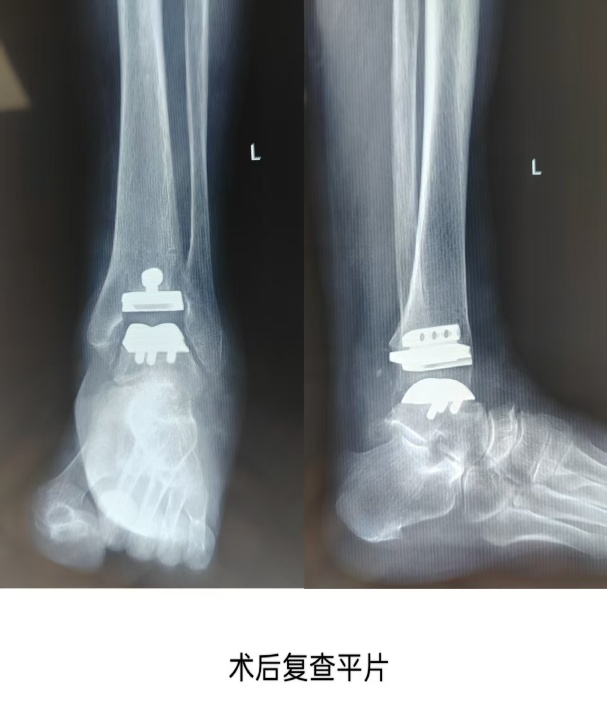

The patient, a 65-year-old female, had progressive pain in the left ankle for 5 years, which worsened with difficulty walking for 2 months. She came to our hospital for diagnosis, and after inquiring about her medical history, conducting a physical examination, and reviewing imaging data, she was diagnosed with “talar necrosis” and was admitted to the hospital. Considering the patient’s high activity demands, it was decided to perform a 3D printed guide-assisted total ankle joint replacement surgery. A multidisciplinary consultation was held with the radiology and surgical anesthesia departments, and after repeated communication with the prosthesis design engineer, the final surgical plan was confirmed and the surgery was conducted, lasting approximately 80 minutes. The patient has now been successfully discharged.